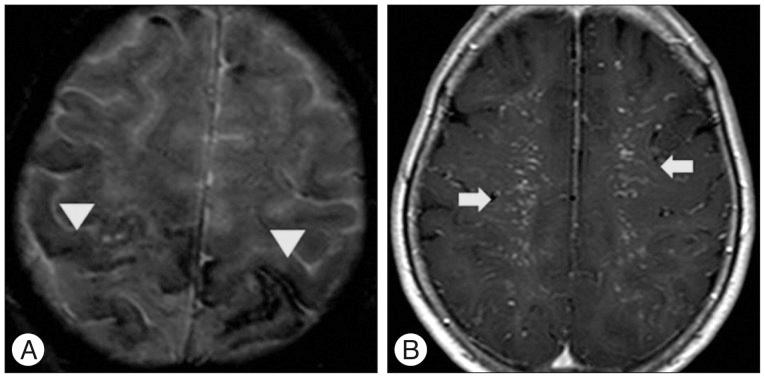

A 66-year-old woman presented with intermittent paraparesis and generalized tonic-clonic seizure. Cerebral angiography demonstrated dural arteriovenous fistula (AVF) involving superior sagittal sinus (SSS), which was associated with SSS occlusion on the posterior one third. The dural AVF was fed by bilateral middle meningeal arteries (MMAs), superficial temporal arteries (STAs) and occipital arteries with marked retrograde cortical venous reflux. Transfemoral arterial Onyx embolization was performed through right MMA and STA, but it was not successful, which resulted in partial obliteration of dural AVF because of tortuous MMA preventing the microcatheter from reaching the fistula closely enough. Second procedure was performed through left MMA accessed by direct MMA puncture following small decortications of cranium overlying the MMA using diamond drill one week later. Microcatheter could be located far distally to the fistula through 5 F sheath placed into the MMA and complete obliteration of dural AVF was achieved using 3.9 cc of Onyx.

一名66岁女性出现间歇性双下肢轻瘫和全身性强直阵挛发作。脑血管造影显示硬脑膜动静脉瘘(AVF)累及上矢状窦(SSS),且与后三分之一的上矢状窦闭塞有关。该硬脑膜AVF由双侧脑膜中动脉(MMA)、颞浅动脉(STA)和枕动脉供血,伴有明显的皮质静脉逆行回流。通过右侧MMA和STA进行了经股动脉Onyx栓塞,但未成功,由于MMA迂曲,微导管无法足够接近瘘口,导致硬脑膜AVF部分闭塞。一周后,使用金刚石钻头在覆盖MMA的颅骨上进行小范围去骨皮质后,通过直接穿刺MMA进入左侧MMA进行了第二次手术。通过置于MMA的5F鞘管,微导管能够置于瘘口远端,使用3.9 cc Onyx实现了硬脑膜AVF的完全闭塞。